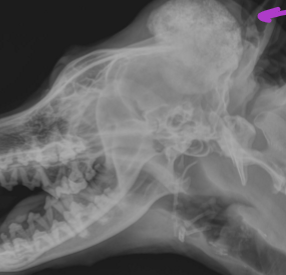

Calvarial hyperostosis

Increased deposition of new bone along the calvarium in puppies